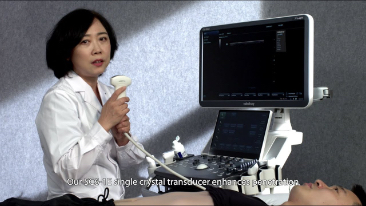

Mindray, ?irketin kuruldu?u gĂŒnden bu yana sĂŒrekli olarak tan?sal do?rulu?u iyile?tirmeye ?al??maktad?r. Devrim niteli?indeki ZONE Sonography? Teknolojisi ile desteklenen Resona 7ânin yeni ZST+ platformu, b?lge g?rĂŒntĂŒsĂŒ alma ve kanal veri i?leme ?zellikleri ile ultrason g?rĂŒntĂŒsĂŒ kalitesini daha ĂŒst bir dĂŒzeye ??kar?yor.

Resona 7, ĂŒstĂŒn dĂŒzeyde g?rĂŒntĂŒ kalitesine ek olarak, vaskĂŒler hemodinamik de?erlendirmesi i?in devrim niteli?indeki V Ak??? ile fetĂŒs CNS tan?lamas? i?in 3 boyutlu veri kĂŒmesinden dĂŒzlem g?rĂŒntĂŒsĂŒ alma konusunda en iyi birime sahip oldu?undan, klinik ara?t?rma yeterliklerini de art?rmaktad?r. En sezgisel, harekete dayal? ?oklu dokunmatik i?letim ile tĂŒm temel klinik ?zellikleri bir araya getiren Resona 7, ultrason yenili?i konusunda ger?ek anlamda yeni dalgalara ?ncĂŒlĂŒk ediyor.